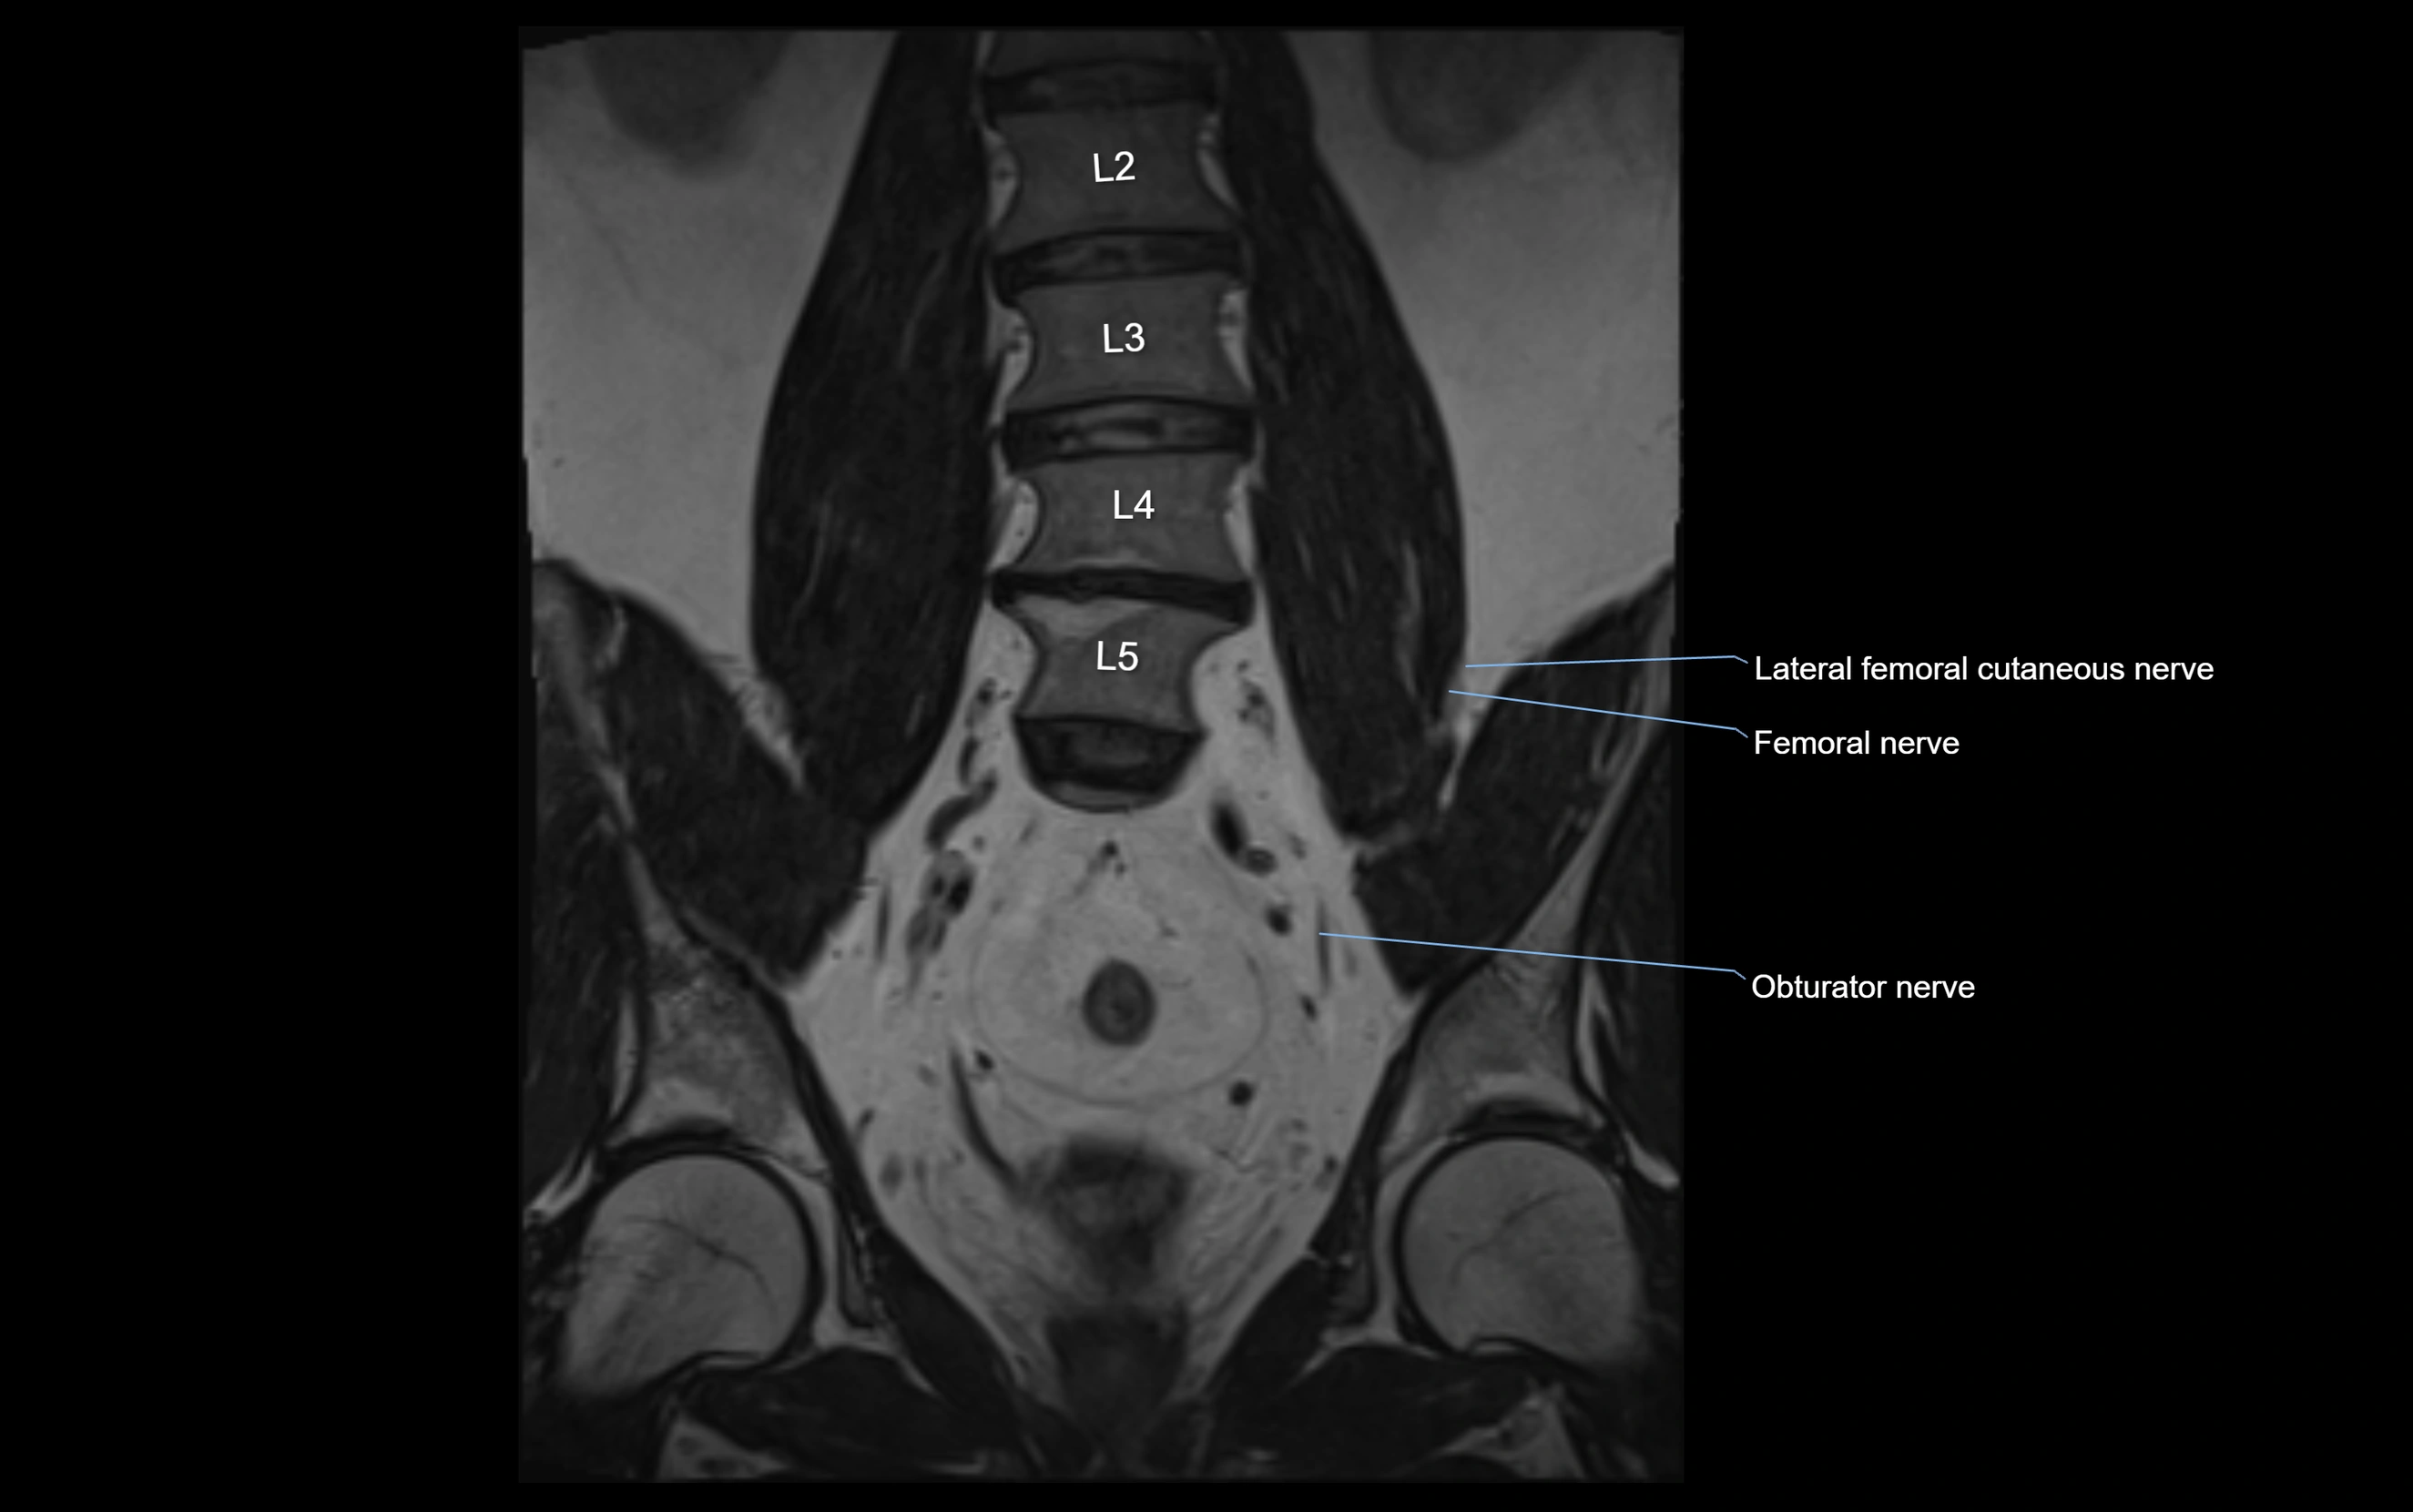

MRI Appearance

T1-weighted images:

• Nerve appears as a very thin low-to-intermediate signal intensity structure

• Surrounded by bright fat, aiding visualization

T2-weighted images:

• Nerve shows intermediate to mildly hyperintense signal compared to muscle

• Pathological involvement appears brighter

STIR (Short Tau Inversion Recovery):

• Normal nerve appears dark

• Inflamed or entrapped nerve appears bright hyperintense

T1 Fat-Sat Post-Contrast:

• Normal nerve enhances minimally

• Pathologic nerve (neuritis, entrapment, tumor infiltration) shows focal or diffuse enhancement

3D T2 SPACE / CISS:

• Nerve appears intermediate to mildly hyperintense compared to muscle

• Surrounded by bright fat or CSF, improving visualization

• Best sequence for mapping small pelvic nerves such as the anococcygeal